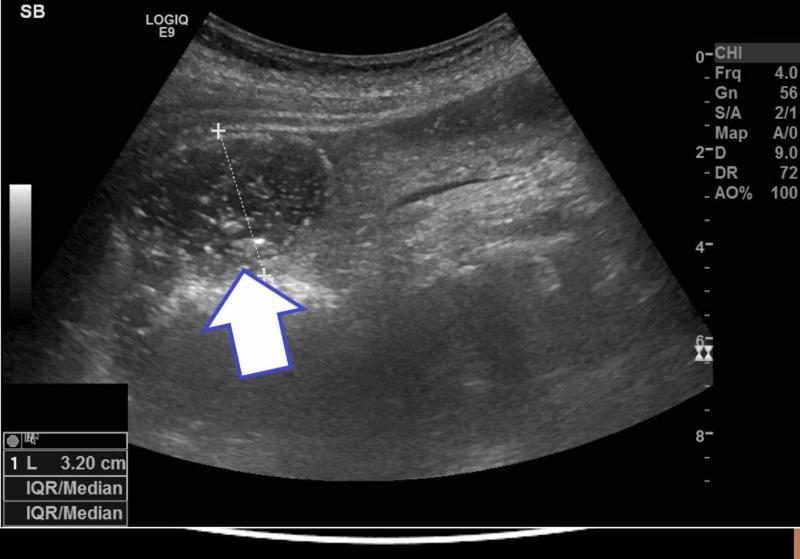

Gallstone ileus is a rare but significant cause of bowel obstruction. An 82-year-old female was admitted to the hospital with abdominal pain and was initially treated for a possible urinary tract infection. Following a surgical review and based on history, clinical examination as well as radiological findings, a diagnosis of gallstone ileus was made. The patient was prepared for surgery; however, whilst awaiting theatre, she spontaneously passed the obstructing gallstone with full resolution of bowel obstruction symptoms. The usual treatment for gallstone ileus is surgical management with an enterolithotomy; nevertheless, this case highlights the importance of close monitoring and adapting a management plan to fit an evolving clinical scenario.

胆石性肠梗阻是一种罕见但重要的肠梗阻病因。一名82岁女性因腹痛入院,最初因可能的尿路感染接受治疗。经过外科会诊,并根据病史、临床检查以及影像学检查结果,诊断为胆石性肠梗阻。患者已做好手术准备;然而,在等待手术期间,她自行排出了阻塞性胆结石,肠梗阻症状完全缓解。胆石性肠梗阻的常规治疗方法是行肠石切除术;尽管如此,该病例凸显了密切监测以及根据不断变化的临床情况调整治疗方案的重要性。